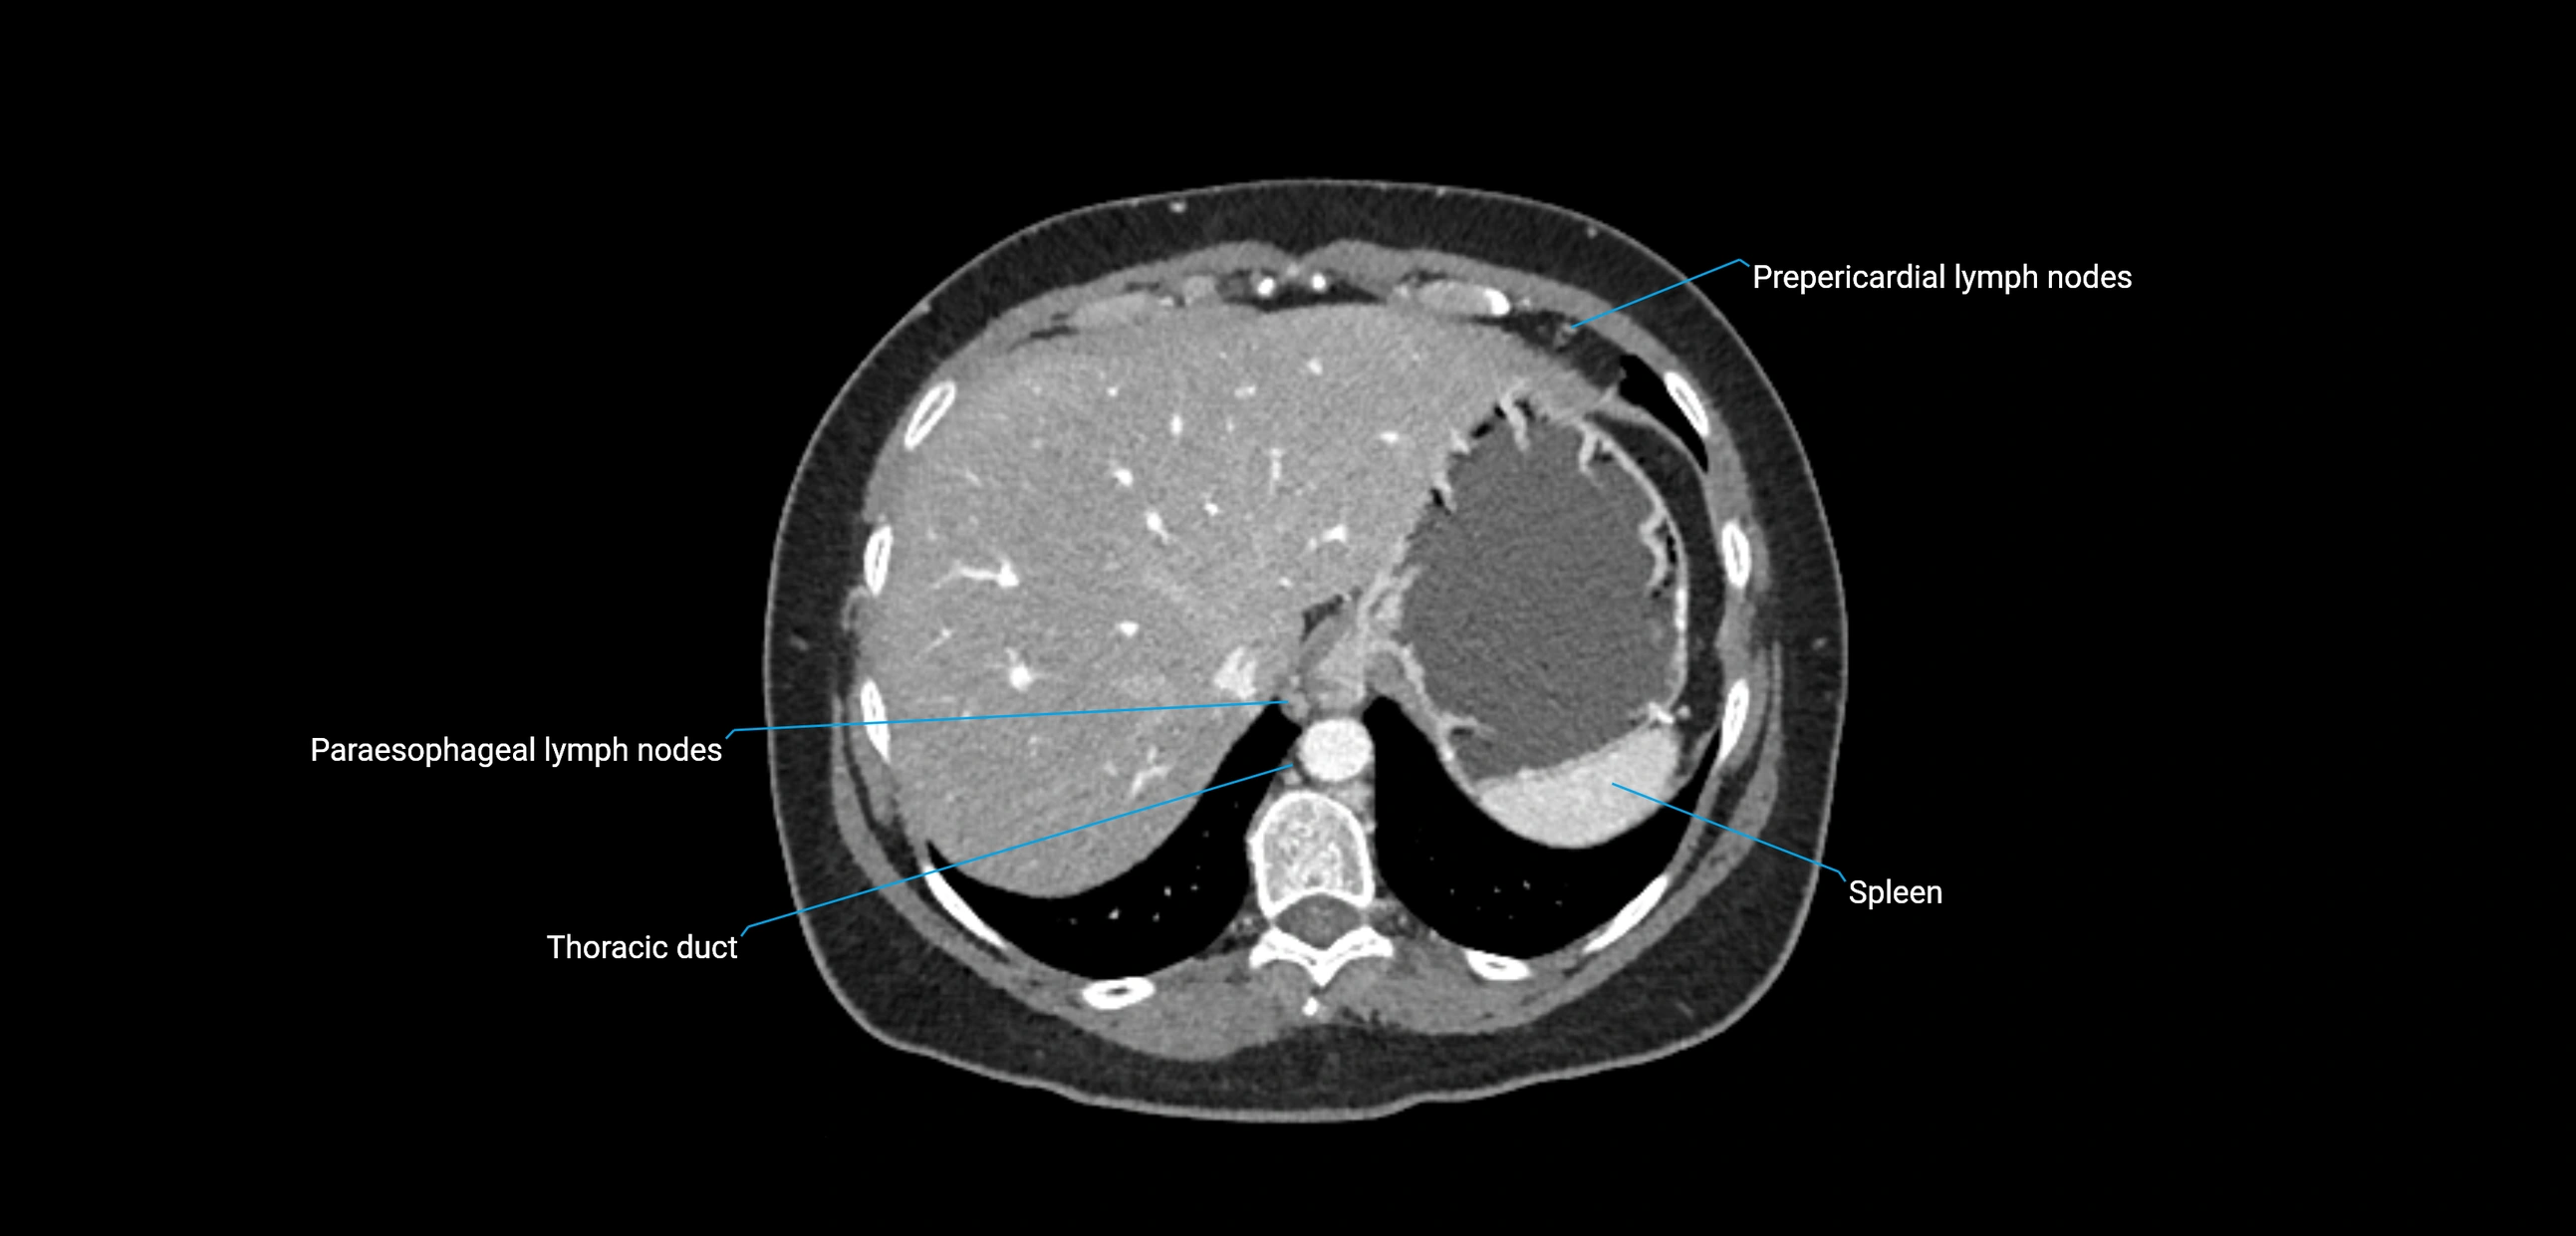

CT Appearance

CT Pre-Contrast:

• Nodes appear as soft-tissue density nodules adjacent to the aorta and IVC

CT Post-Contrast:

• Normal nodes enhance homogeneously

• Malignant nodes may show heterogeneous enhancement, central necrosis, or conglomerate formation

• Size >1 cm short axis is suspicious, though morphology and distribution are equally important